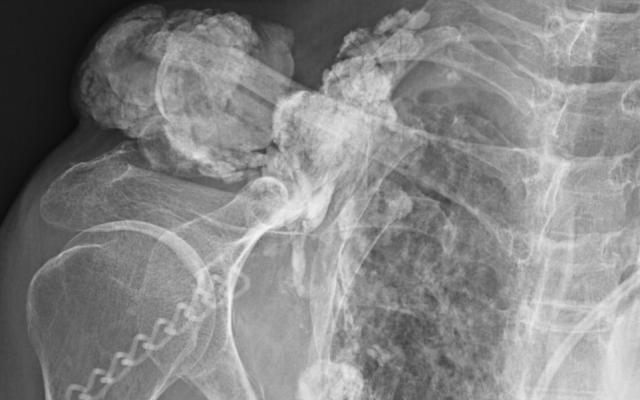

Dit artikel is alleen beschikbaar als PDF.Lees de PDF Artikelinformatie Online verschenen op 25 februari 1972 Citeer dit artikel als Ned Tijdschr Geneeskd. 1972;116:897-8 Heb je nog vragen na het lezen van dit artikel? Check onze AI-tool en verbaas je over de antwoorden. ASK NTVG Ook interessant Diagnose in beeld Een vrouw met een zwelling op de schouder Beeldquiz Een vrouw met een zwelling op de schouder Nieuws Vrouwenvoeten: hoe ouder hoe breder Meer gerelateerd … Reacties Login om een reactie te plaatsen